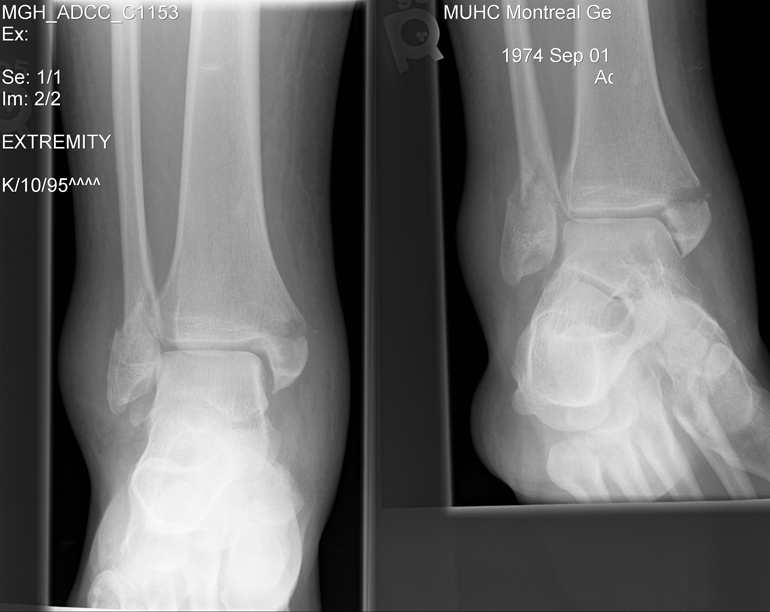

This is the break (both sides):

0010003.jpg